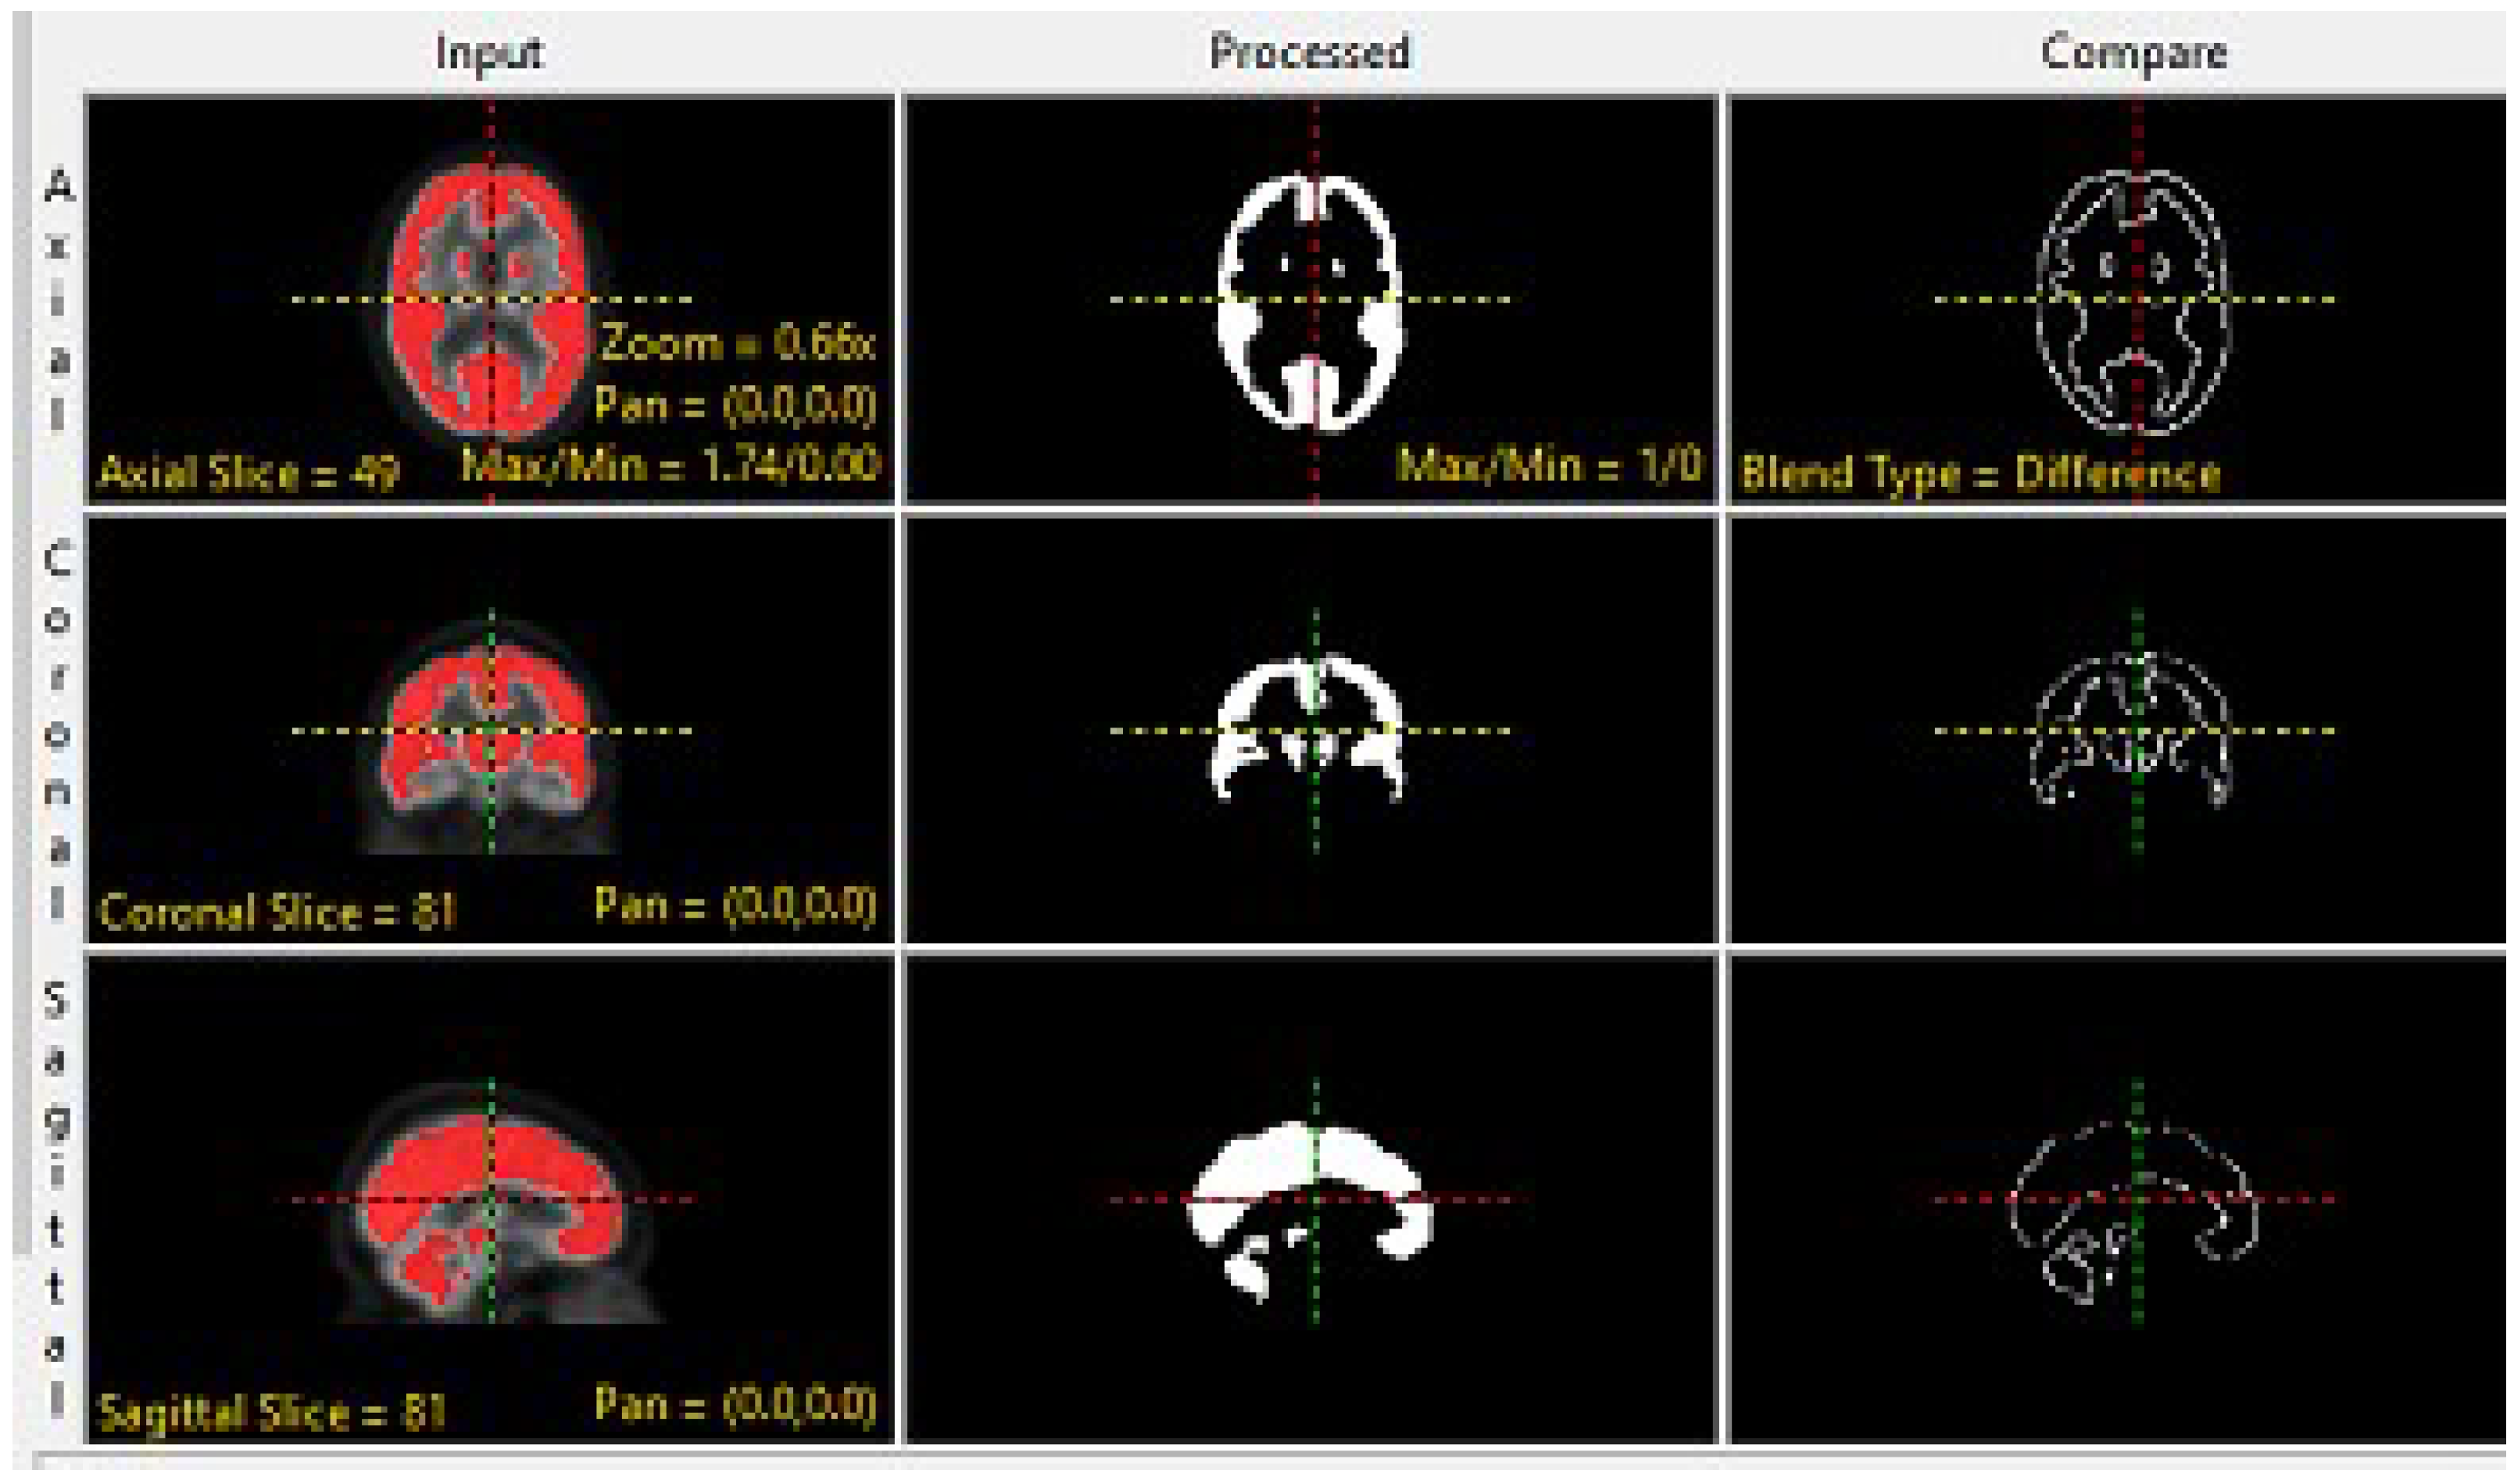

2.1. Preprocessing of MRI and PET Images

2.2. Proposed Fusion Technique of MRI and PET